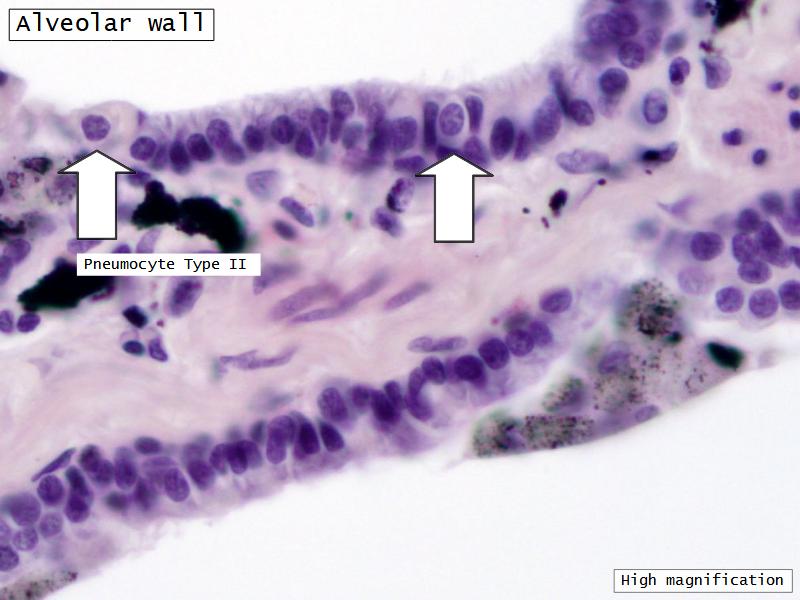

What cells are present?

Components of the Blood-Air Barrier?

- Respiratory bronchioles

- Conducting -> Respiratory

- Simple cuboidal epithelium

- Secretory cells

- Alveoli